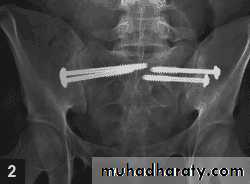

Operative treatment

• Indications• Symphysis diastasis greater than 2.5 cm.

•Vertical instability of posterior hemipelvis

• Sacral fracture with displacement greater than1 cm